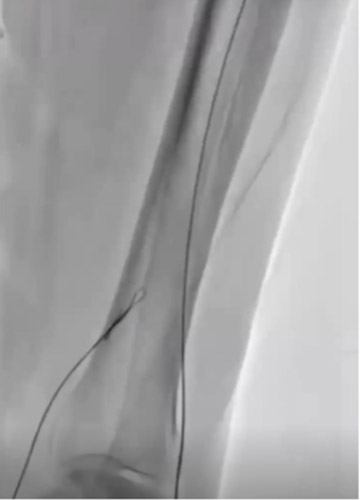

DAは閉塞していたが内腔はあるので穿刺を検討したが、難しいと判断しPTAを穿刺した。PTA経由でATAにレトログレードアプローチを行いDAからシースを挿入するため、1gワイヤーを進めたがATA(Anterior Tibial Artery)方向へワイヤリング出来ないため、Zizai™をPOP方向へ進め造影した(図3)。ATA入口部は狭窄しており、更に末梢は閉塞していることを確認した。ATA入口部へワイヤー通過に成功し急峻な角度ではあったがZizai™を追従させ(図4)、ATAは閉塞血管でありワイヤールートはSubでも良いと判断しワイヤーナックルにて末梢まで進めた。DAを18G針で穿刺をしワイヤーランデブーに成功した(図5)。その後、DAに4Frシースを挿入し、2.5㎜径バルーンでATAを拡張したあと、PTAのワイヤーとZizai™を抜去後にアプローチサイトの止血を行い、ATAの4Frシースからガイディングシースへ入れ替えを行った。